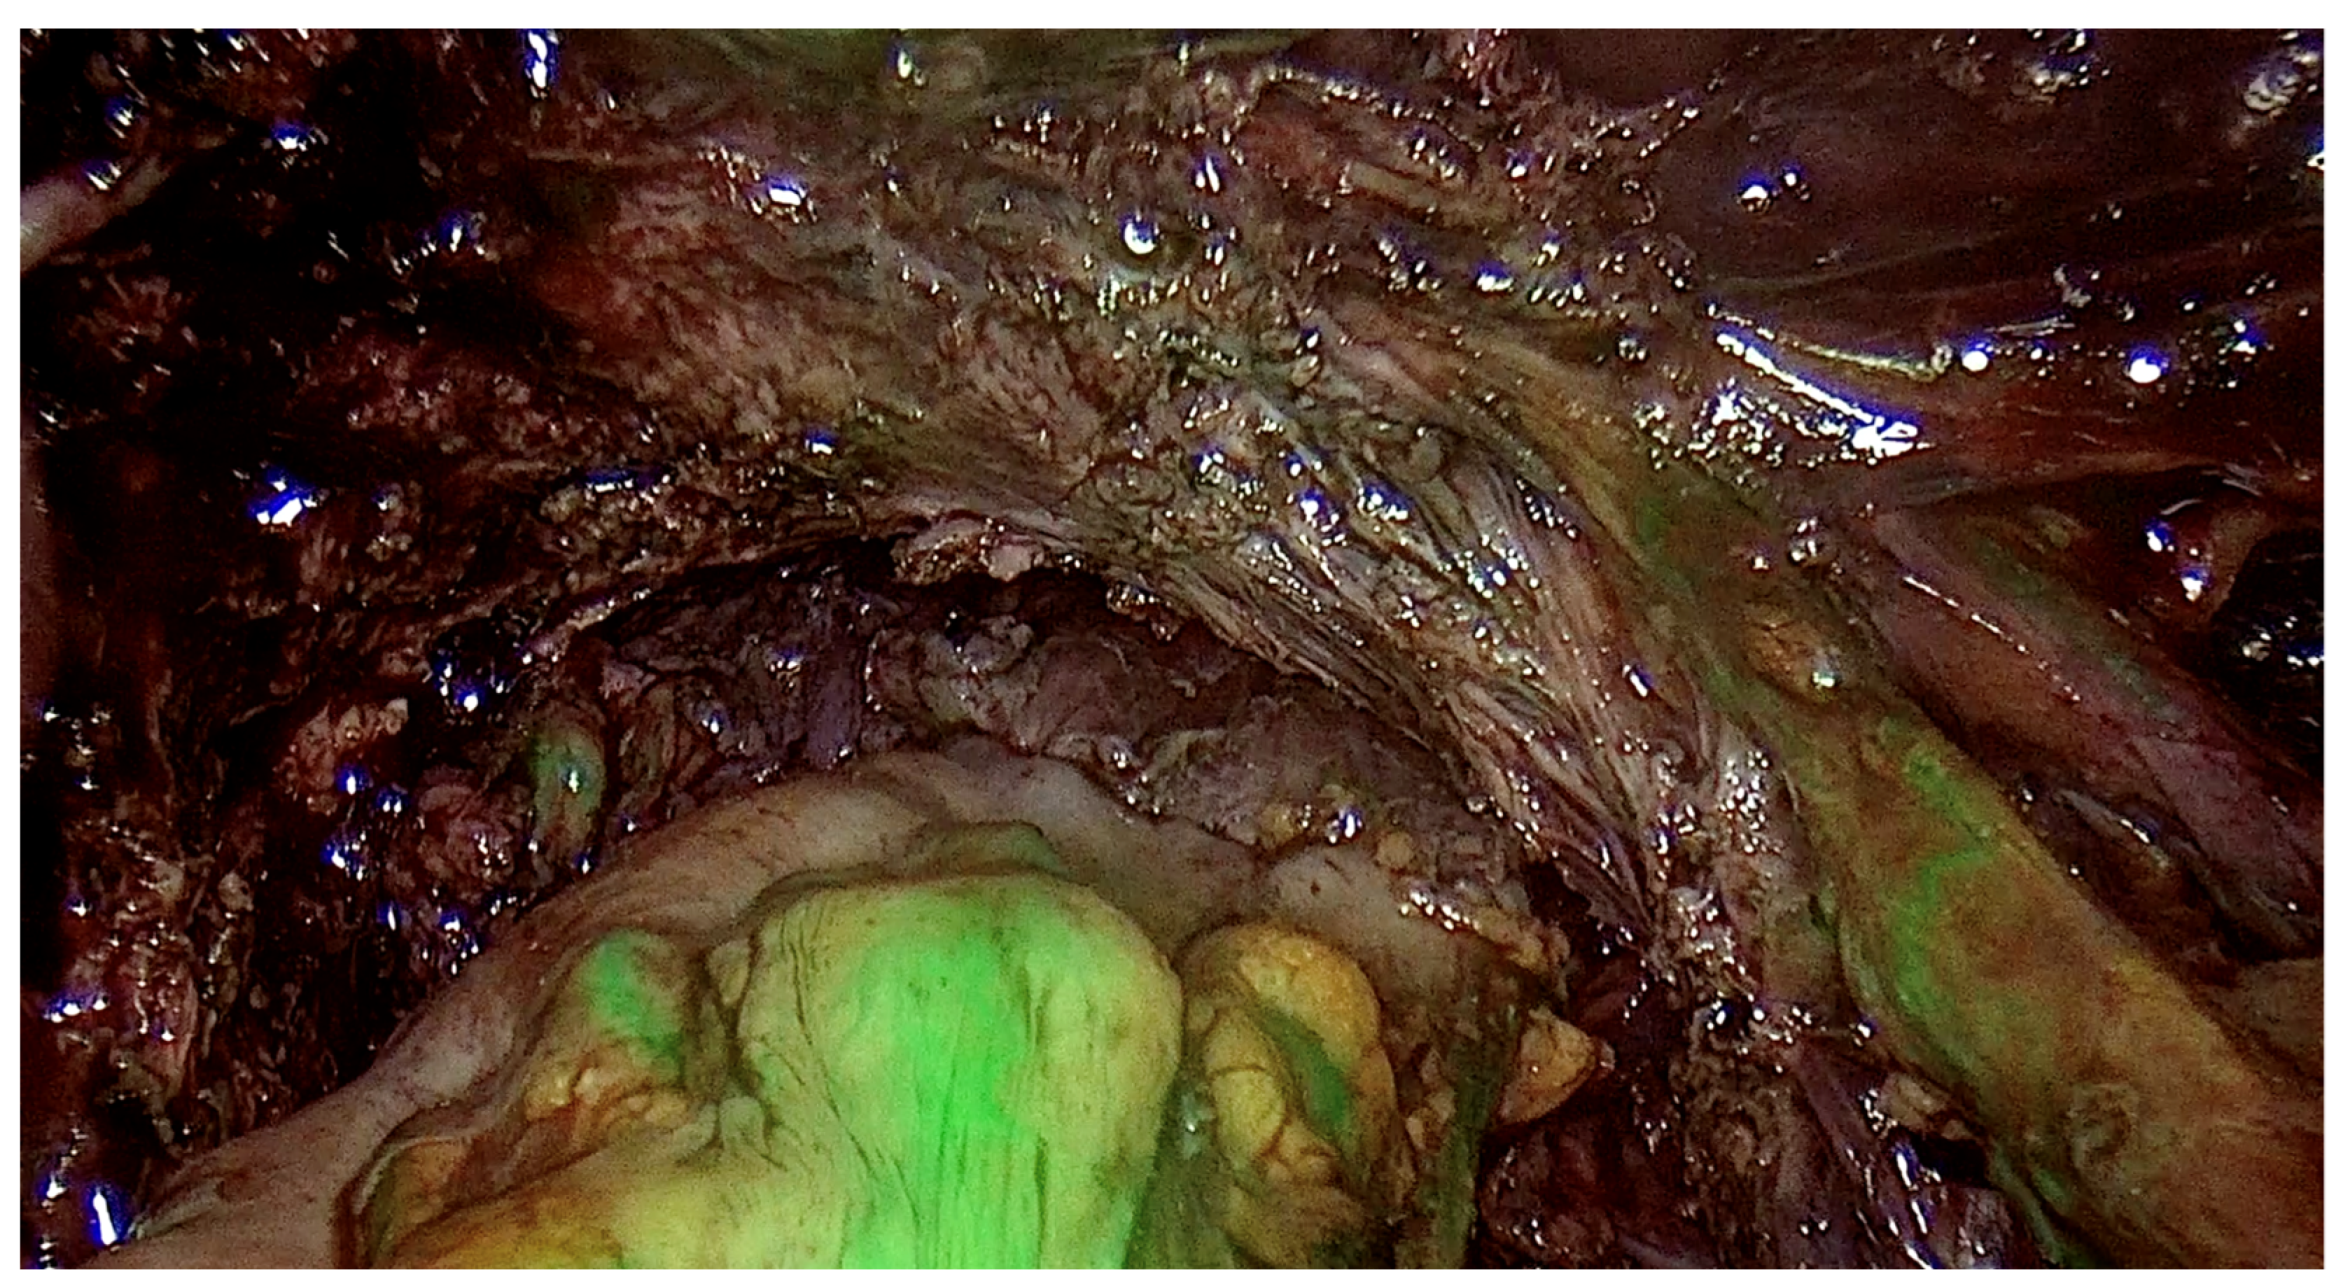

2.5. Surgery

- Improves diagnostic efficiency as the surgeon performing the examination learns to analyze ultrasound images more effectively, which can be compared with images of endometrial changes during surgery. This correlation contributes to better assessment in subsequent examinations;

- 5.